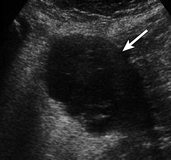

İyi huylu ve kötü huylu yumurtalık kistlerini ve tümörlerini hızlı ve güvenilir bir şekilde ayırt etmek çok önemlidir. Bu sayede cerrahi müdahale ve hastalığın seyri iyileşir. Gasthuisberg Kampüsü Üniversite Hastanesi Jinekoloji Anabilim Dalı Başkanı Prof. Dr. Dirk Timmerman tarafından yapılan araştırma, ultrason takibinde birkaç püf nokta ile iyi ve kötü huylu tümörlerin birbirinden ayırt edilebileceğini öngörüyor.

Dr. Timmerman’ın geliştirdiği ultrason kriterleri başında tümörün dış görünüşü geliyor. Asimetrik şekil, katılık, çap, kistin iç duvarı, kan akışı ve kalsifikasyonlar. Eğer iyi huylu bir kist bu kriterlerden birini taşıyorsa veya kötü huylu bir tümör bu kriterlerden birini taşıyorsa, iki alt kategoride ele alınır. Bu işlem ameliyat olan 2000 kadın üzerinde incelendi. Hastaların %77’inde bu kriterlerin uygulanabilir olduğu görüldü. Araştırmacılar, bu kriterler haricinde başka bir durum söz konusuysa veya tümör hem iyi hem de kötü huylu olma özelliklerini taşıyorsa, uzman bir hekim tarafından kapsamlı bir ultrason işlemi yapılmasını önerdi.